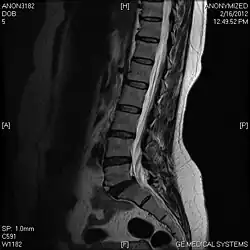

Limbus vertebra

A limbus vertebra is a bone tubercle formed by bone trauma on a vertebral body, bearing a radiographic similarity to a vertebral fracture. The anterior-superior corner of a single vertebra is the common site for this defect although it can also be seen at the inferior corner as well as the posterior or anterior margin. Anatomically, it is assumed to be an intra-vertebral body herniation of the disc material occurring during adolescent growth spurt when the ring apophysis has not yet fused. It was first described by Schmorl in 1927[1] and later in detail by Leif Sward and Adad Baranto.

Viewed in a lateral radiograph, it appears as a triangular shaped bone fragment, not unlike an anterior lip fracture, but with softer edges.

Limbus vertebra is not always symptomatic, but severe cases may lead to more serious pathological conditions and chronic pain. In rare instances, a posterior limbus vertebra has been described causing radiculopathy due to nerve root compression.[2]